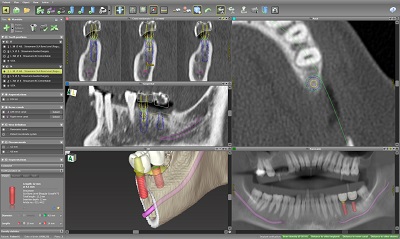

ガイデッドサージェリーを

使用した正確かつ安心・安全

CTデータをもとに、ガイデッドサージェリーを作製・使用します。穴のあいたマウスピースのような形をした装置を使用することで、インプラントをシミュレーション通りの位置・角度・深さで埋入します。

CTデータをもとに、ガイデッドサージェリーを作製・使用します。穴のあいたマウスピースのような形をした装置を使用することで、インプラントをシミュレーション通りの位置・角度・深さで埋入します。

また、顎の骨の量・質を三次元的に評価できる歯科用CTで検査により、正確に診断いたします。

口腔内検査、レントゲン検査、CT検査などを行い、診断します。

口腔内検査、レントゲン検査、CT検査などを行い、診断します。

CT検査では、顎の骨の量や質、神経や血管の位置などを正確に調べることができます。